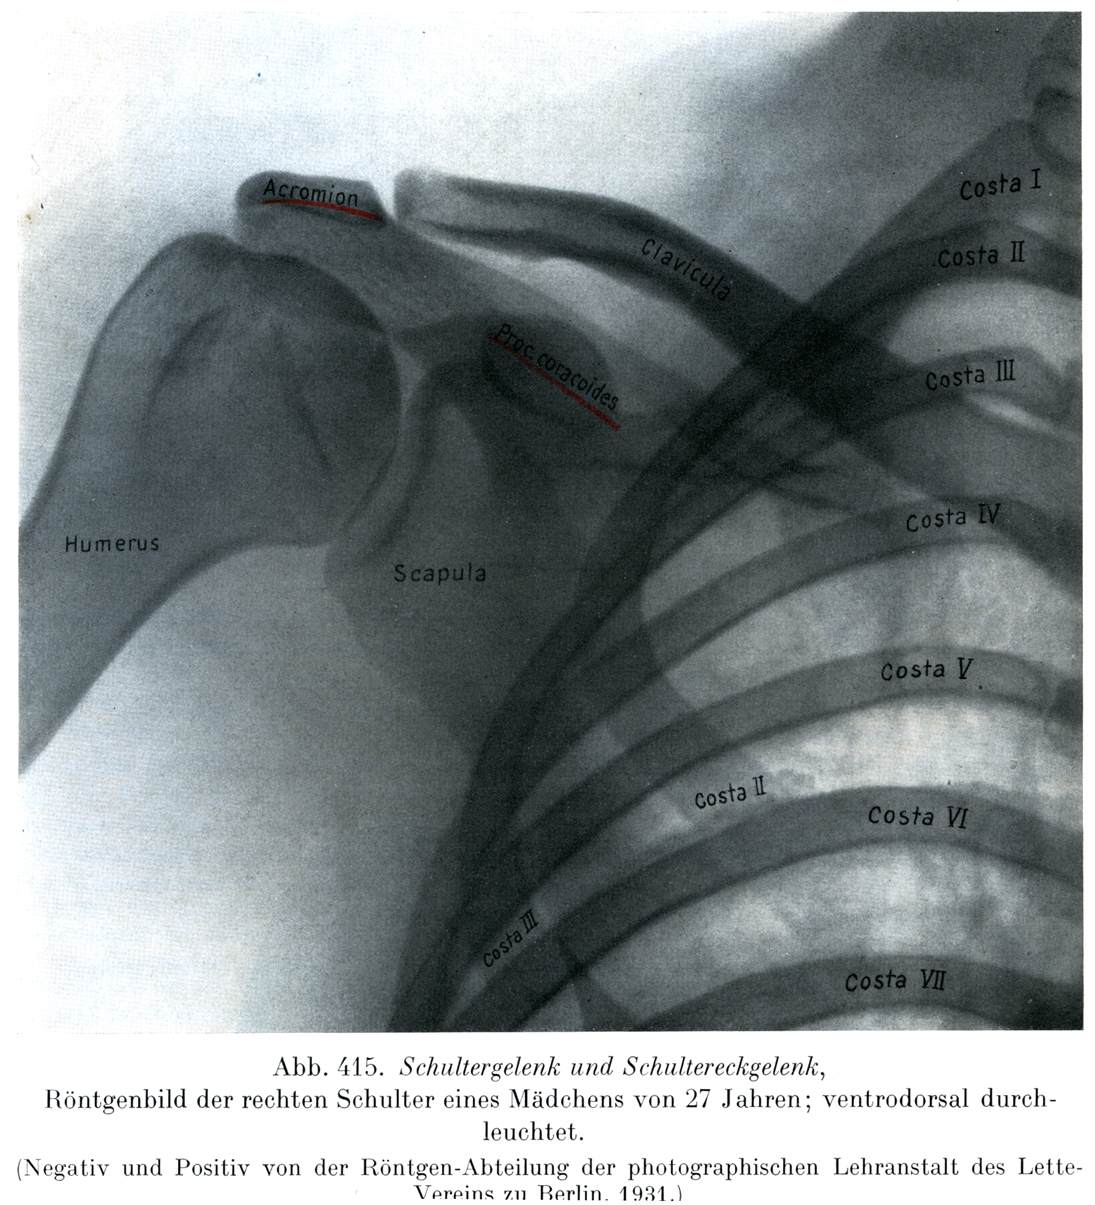

肩関節と肩鎖関節

27才の処女の右肩のレントゲン像,腹背照射.